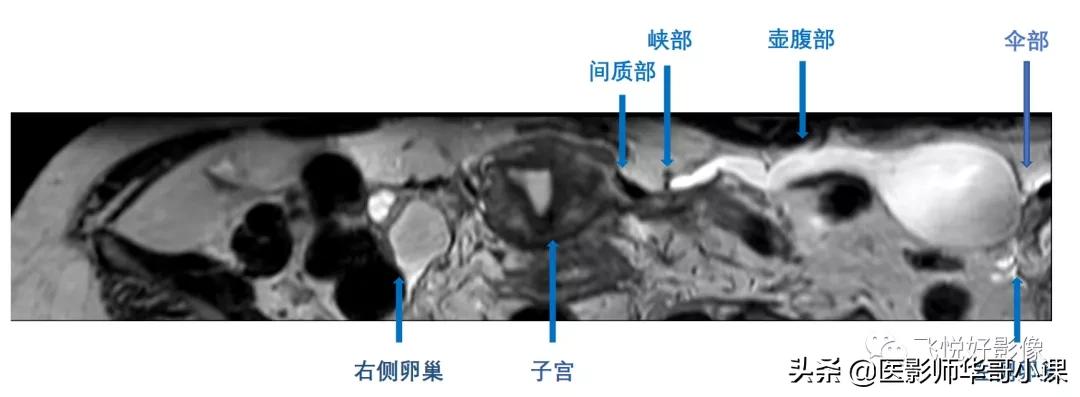

图6.卵巢、输卵管解剖

育龄期妇女双侧输卵管长约8-15cm,直径约1-4mm,起自双侧子宫角,横向延伸至同侧卵巢,分为间质部、峡部、壶腹部和伞部。间质部、峡部短而窄,壶腹部相对宽大,伞部呈漏斗状,开口于腹腔。